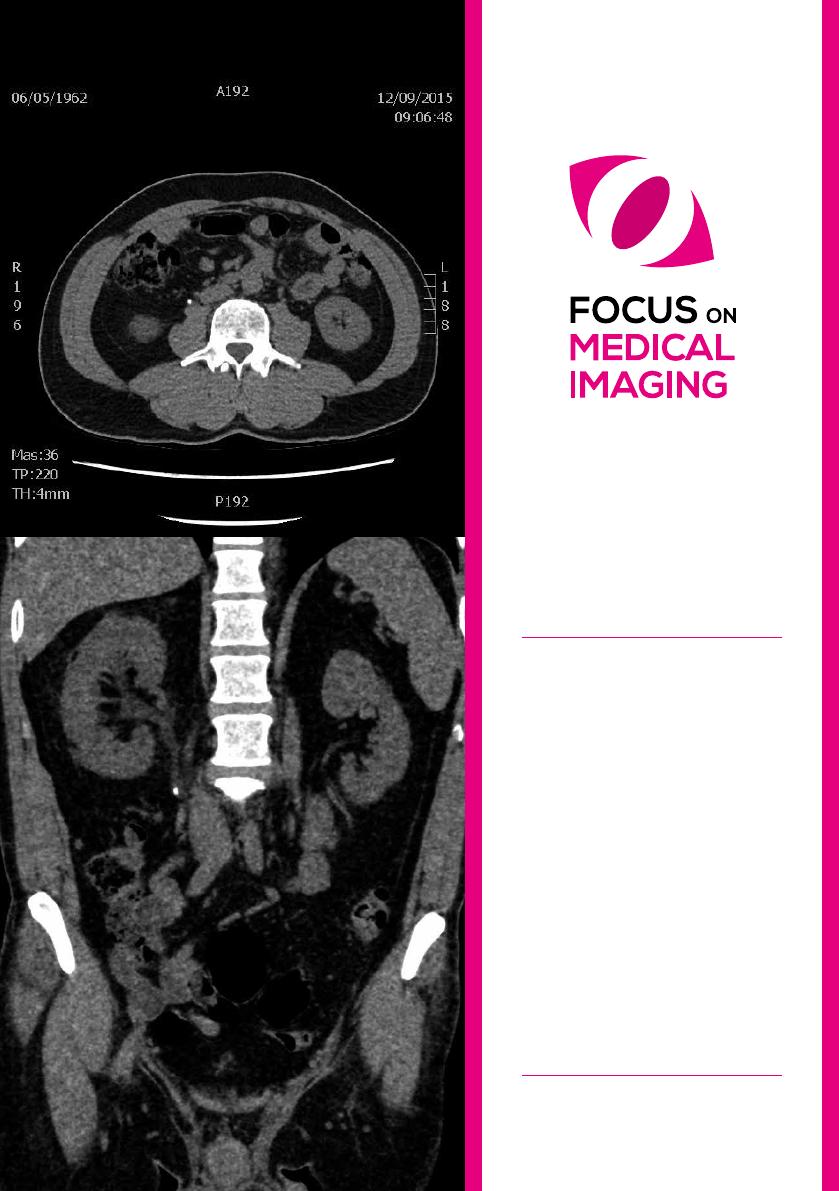

Diagnostic

Un examen radiologique déterminera le dia-

mètre du calcul, sa localisation et l’eet sur les

reins (et ses fonctions).

Le diagnostic clinique d’un calcul urétéral est

(le plus souvent) confirmé par un examen ra-

diologique, surtout quand un patient sympto-

matique se présente aux urgences.